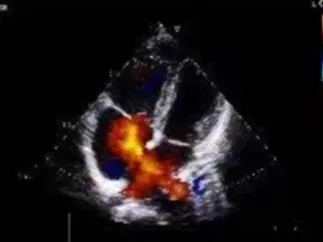

术中复测

超声可见房间隔连续中断,彩色多普勒可见过隔血流

测量房间隔缺损直径最大为23.9mm,房间隔总长53.8mm